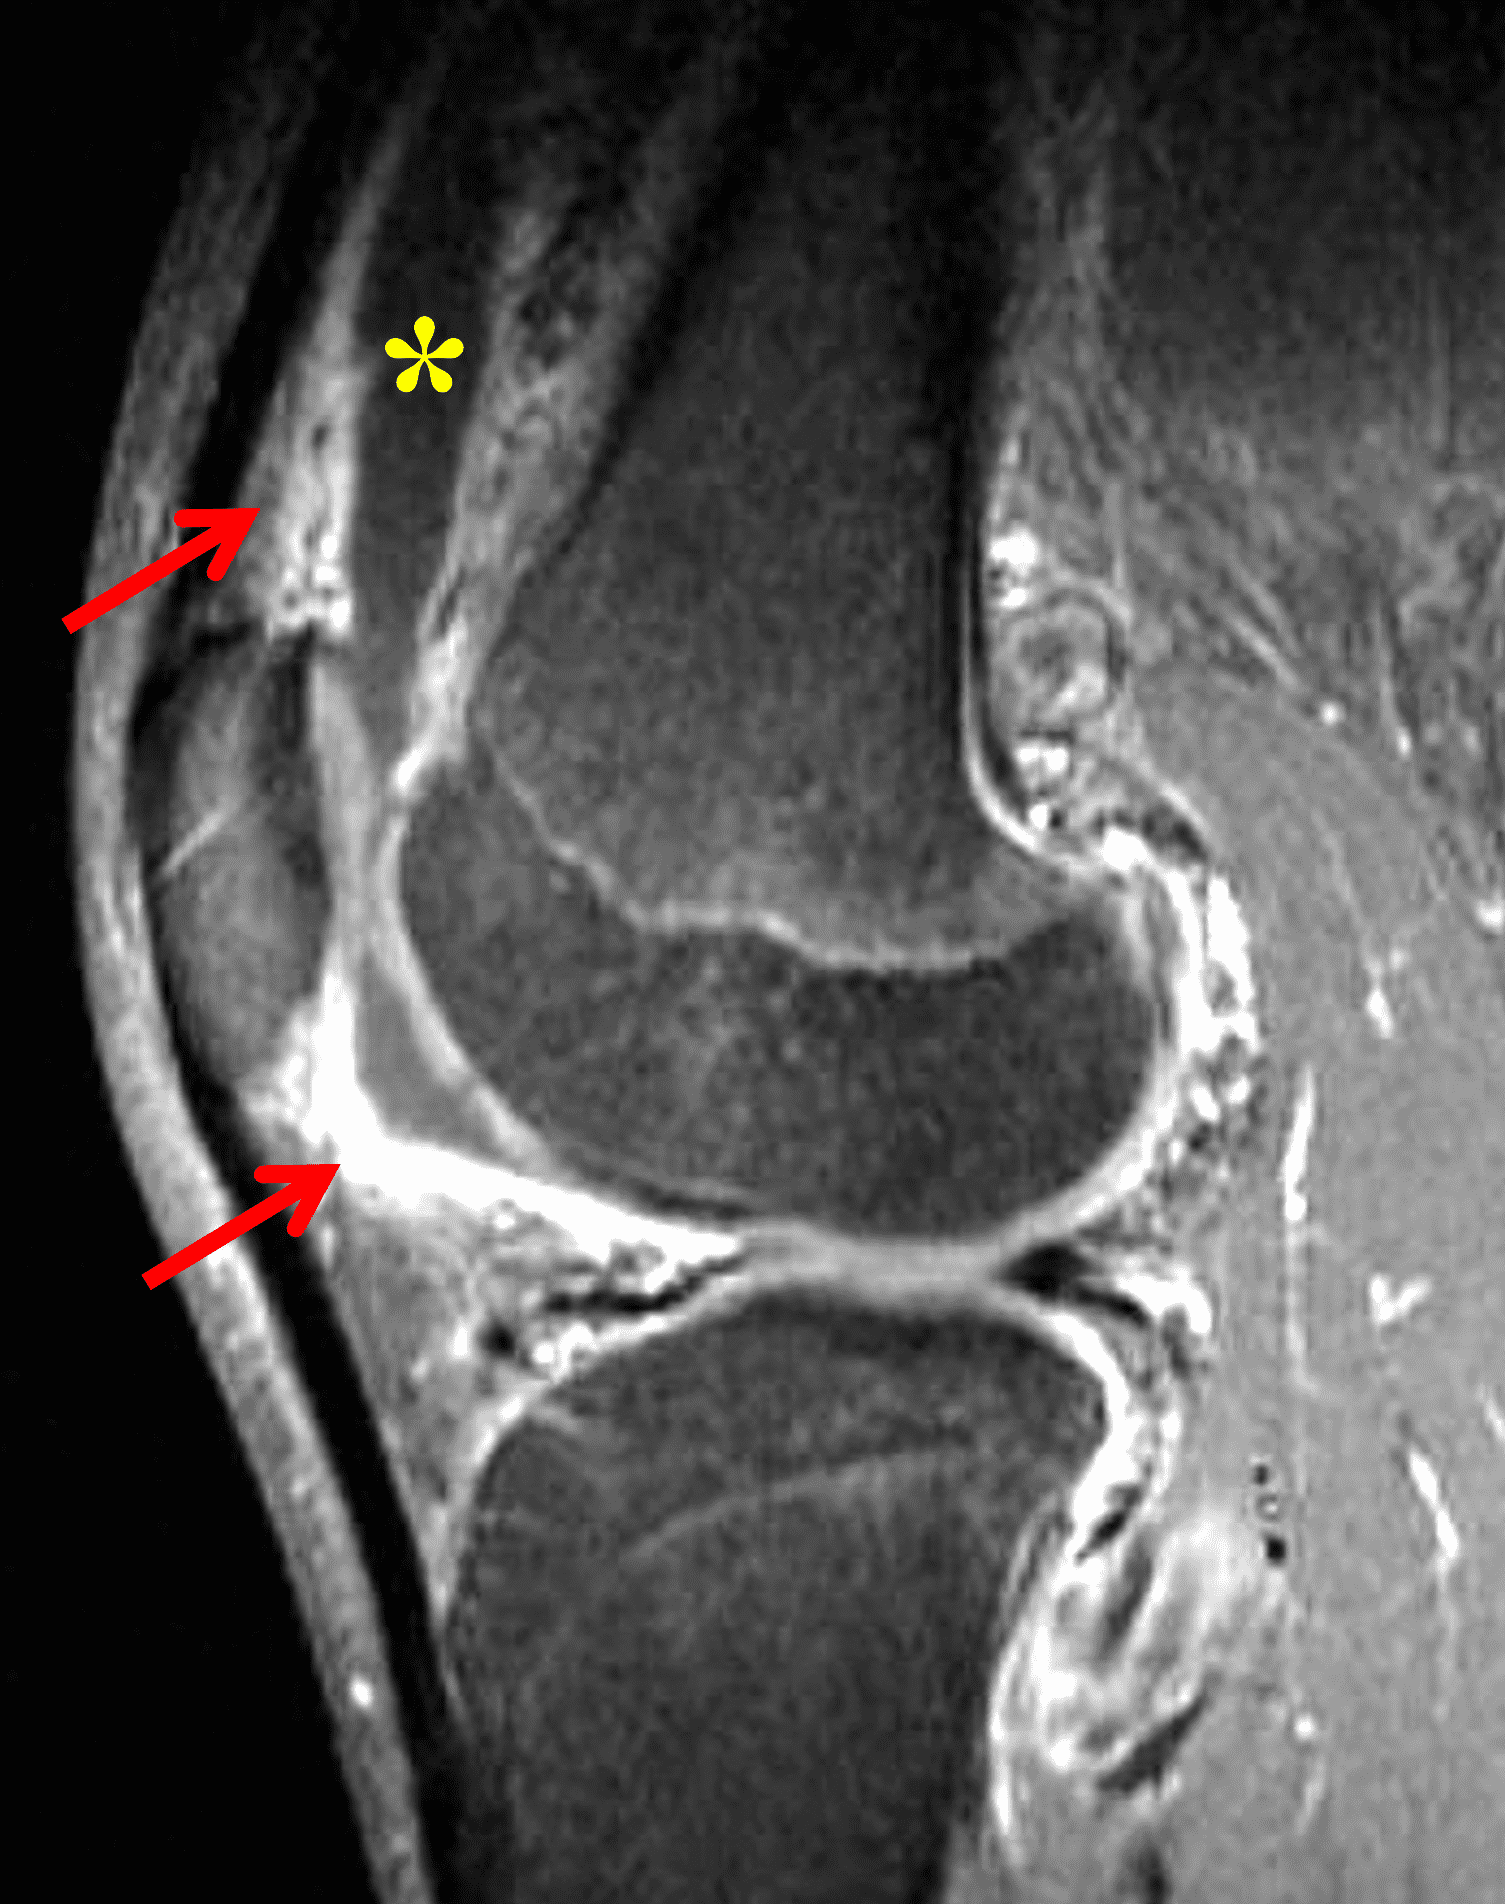

Figure 2: (2A) The coronal image shows a large effusion and severe hypertrophic synovitis (asterisks) in the knee. (2B) On the sagittal image the hypertrophic synovium (asterisks) involves the suprapatellar and infrapatellar recesses as well as the anterior and posterior intercondylar notch. A reactive lymph node (arrow) is present in the popliteal fossa. (2C) The axial image demonstrates myositis (arrows) involving the popliteus and peroneus longus muscles. Note the preserved articular cartilage, lack of erosions, and the absence of subcutaneous or marrow edema.

The causative spirochete invades the synovium, triggering a host inflammatory response that leads to synovial hypertrophy and inflammation, resulting in the characteristic clinical symptoms and imaging findings associated with Lyme arthritis.2 Common MR findings associated with Lyme arthritis include synovitis, joint effusion, popliteal lymphadenopathy, and myositis predominantly involving the popliteus (Figure 4).2,3,9 In contrast to acute septic arthritis due to more common bacteria, subcutaneous edema, marrow edema, erosions, and osteomyelitis are uncommon (Figure 4C).

Figure 4: Lyme arthritis. Fat-suppressed, fluid-sensitive images. (4A) Transverse image shows severe proliferative synovitis in the anterior and posterior joint recesses (arrows). Note the lack of surrounding subcutaneous edema. (4B) In addition to synovitis, the sagittal image shows multiple reactive lymph nodes (red arrows) and popliteal myositis (white arrow). (4C) Coronal image also shows patchy non-joint centered marrow edema in the distal femur and proximal tibia (asterisks), which is uncommon in Lyme disease compared to acute septic arthritis.